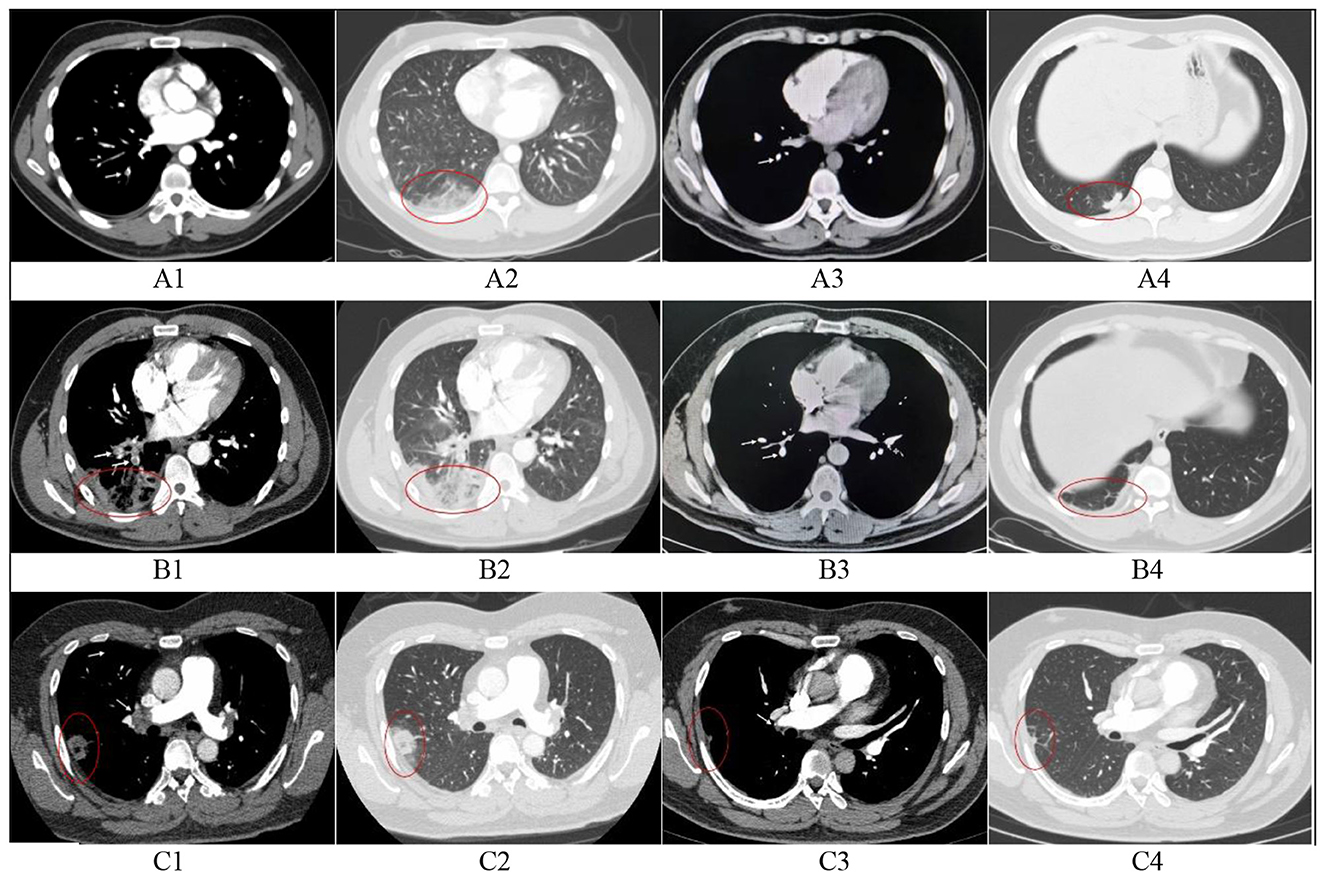

You don't have a Frontiers account ? You can register here

Objective: To analyze the clinical characteristics of pulmonary infarction in elderly patients with pulmonary embolism. Methods: We conducted a single-center retrospective study of 71 patients with pulmonary infarction (PI) secondary to pulmonary embolism (PE) confirmed by CTPA between January 2016 and December 2021. Participants were stratified into elderly (≥65 years) and non-elderly (<65 years) groups. We compared baseline characteristics, laboratory/imaging findings, Wells scores, PE severity, diagnosis and treatment using chi-square and Mann-Whitney U tests. Results: PI occurred in 17.1% (71/414) of PE cases, comprising 36 elderly patients and 35 non-elderly patients. Significant differences were observed in pleuritic chest pain, hemoptysis, cardiovascular disease, cerebrovascular disease, pulmonary hypertension, and ECG changes between the two groups (P<0.05). PI occurred predominantly in the right lung and in lower lobes. No significant differences were observed in infarction location, number, or imaging signs between groups. The comparison of PE risk factors and Wells scores showed no significant differences. The elderly group showed a higher proportion of intermediate-high risk and a lower proportion of low-risk in PE severity classification (P<0.05). During the medical consultation process, elderly exhibited higher non-emergency/respiratory first-visit rates than younger (P<0.05). Similarly high rates of antibiotic therapy were observed in both groups (P>0.05). Conclusion: Elderly PI patients have less typical chest pain, hemoptysis or ECG changes, a high proportion of comorbid cardiovascular/cerebrovascular diseases, and a higher rate of mismatch in the first visiting department. Clinicians should recognize the atypical presentations of PI in elderly patients and pay increased attention to this population.